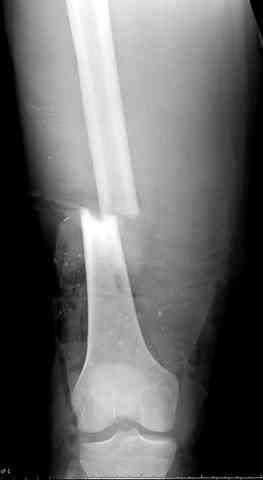

Я бы выполнил более стабильную фиксацию (а у меня есть подозрения в нестабильности отломков - компоновка минимальная, стержни проведены близко друг от друга, имеется выраженное воспаление тканей вокруг раны). Добавил бы стержни в данном аппарате или бы наложил спицестержневой аппарат.

Наверное, оптимальное решение для закрытие раны на данном неудобном уровне - микрохирургическая пересадка мышечного или кожно-мышечного лоскута (рис. 1, 2, 3).